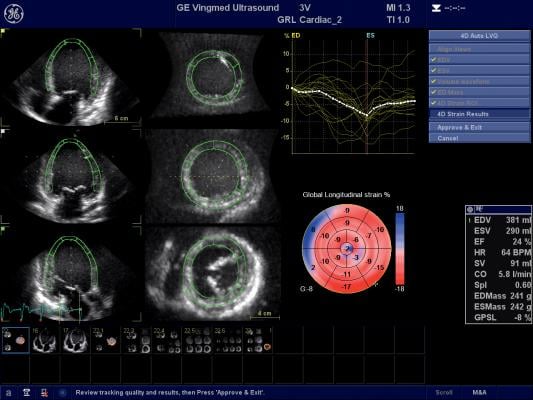

June 13, 2016 – After following a large sub-set of patients, researchers found that by using strain echocardiography they could accurately predict which patients were likely to have complications from hypertrophic cardiomyopathy (HCM). This is important because HCM is common, but often undetected, and one of the leading causes of sudden cardiac death in young adults.

“HCM is the most common inherited cardiac condition with several disabling and life-threatening complications. Global longitudinal strain was able to independently predict key outcomes in HCM and therefore has the potential to become an essential tool in HCM risk assessment,” said Hongyun Liu, M.D., of the Johns Hopkins HCM Center of Excellence, Baltimore.

Conventional and strain echocardiography were performed in 400 HCM patients who were followed for 37 months to obtain the necessary data. Strain echocardiography is an advanced but growing cardiovascular diagnostic technique that is a sensitive and powerful way to assess patient outcomes.